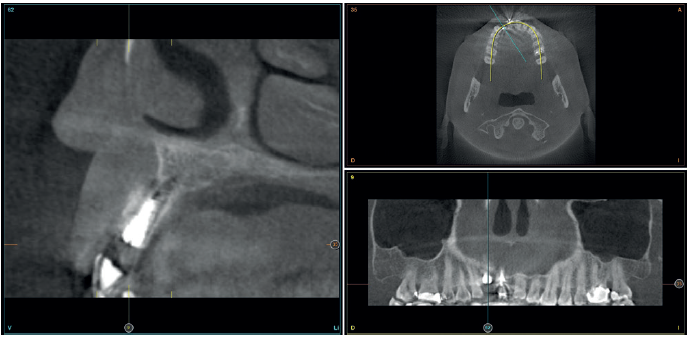

Para continuar con el estudio del caso se realiza un Cone-Beam donde poder observar tridimensional ente la posición del implante situado en posición 1.2. En los cortes seccionales se visualiza completamente situado hacia vestibular con una reabsorción casi completa de la cortical ósea de esta área, lo que explica los problemas de tejido blando subyacente. En la radiografía periapical se observa la posición del implante con respecto a los dientes adyacentes

(Figuras 5 y 6). Con esta imagen se procede a la apertura de un colgajo y la explantación del implante. Se retira también la corona situada en el diente 1.1 para poder realizar otra corona que servirá para apoyar el provisional en extensión para la zona del 1.2, mientras cicatriza la primera intervención. En este primer abordaje se coloca también un injerto en bloque obtenido de la rama mandibular que se fija con un microtornillo en la zona a regenerar donde se ha perdido la cortical vestibular. Una vez fijado y posicionado, se rellena alrededor del injerto en bloque con hueso particulado obtenido con un bone-scraper de la misma zona donante embebido en PRGF-Endoret para una mejor fijación y viabilidad celular (Figuras 7-9).

Cuatro meses después, se realiza un nuevo Cone-Beam dental para poder cuantificar la ganancia obtenida en anchura con el procedimiento regenerativo. Se observa en el corte seccional como se ha logrado una anchura de cresta de más de 7 mm y una regeneración completa del reborde alveolar, lo que permite la inserción de un nuevo implante dental en la posición adecuada (Figura 10). En la reentrada quirúrgica se constata la información del Cone-Beam con una integración total del material de injerto, tal como se muestra en las imágenes clínicas en el momento de la elevación del colgajo para la inserción del implante (Figuras 11 y 12). Se procede a la retirada del microtornillo y la colocación del implante, que se realiza mediante la compresión vestibular del injerto para ganar de esta manera aún más contorno en esta área (Figura 13). El implante se deja en una fase quirúrgica, con un pilar de cicatrización bajo que permita una localización posterior del mismo sin una cirugía agresiva del tejido blando para cuando se inicie la confección de la prótesis. El provisional sigue siendo una pieza en extensión desde el diente 1.1.